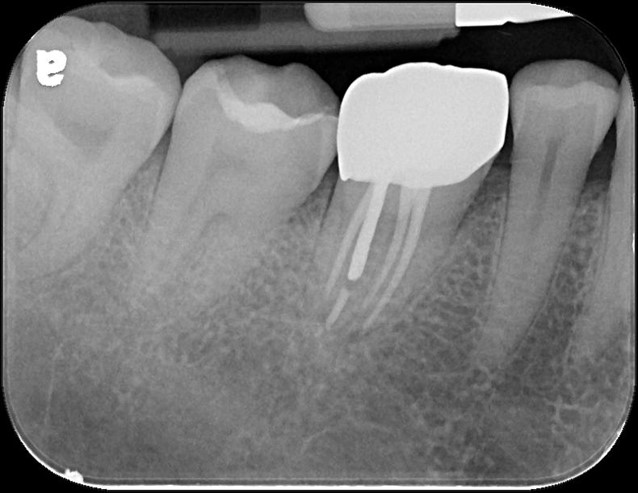

治療前,右下第一大臼齒冷熱敏感

治療前,蛀牙已侵犯至牙髓

顯微根管治療

全鋯冠

治療後,牙周咬合良好

治療後,密合度良好